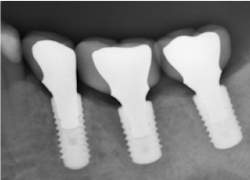

Implants are not tooth analogues. They are foreign bodies that can maintain a biological equilibrium in the surrounding hard and soft tissues. The most significant differences to teeth relate to their lack of resilience, due to their ankylosed state, and reduced proprioceptive feedback, essential for modulating occlusal forces (figure 3). However, the remaining teeth in segmental reconstructions can usually compensate for the latter.

Figure 3